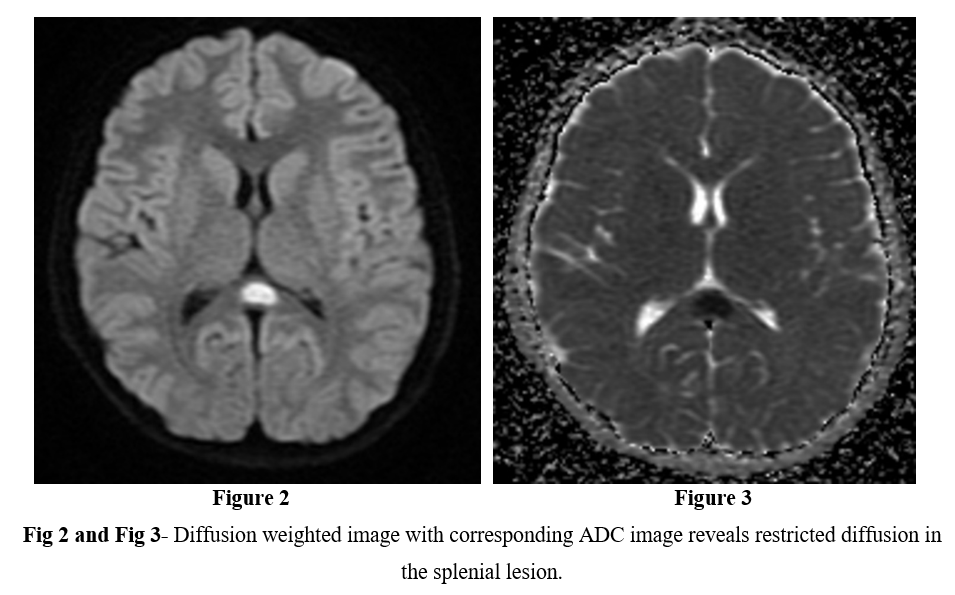

MRI of the brain with contrast was performed using 1.5 tesla scanner (GE Medical System). An oval well-circumscribed lesion was noted in the splenium of the corpus callosum in the midline (Figure 1). The lesion displayed restricted diffusion with low ADC values (Figures 2 and 3). No evidence of mass effect or perifocal edema was seen. No evidence of abnormal post-contrast enhancement was noted (Figure 4). No lesions are seen in the periventricular white matter and in the subcortical U fibers. In view of the clinical history and morphology of the lesion was read as reversible splenial lesion syndrome (RESLES). The differential diagnosis that were considered included ADEM, multiple sclerosis, encephalitis and glial tumor.

The syndrome is characterised by cytotoxic lesions in the splenium of the corpus callosum, manifesting as areas of low diffusion on diffusion weighted MRI images and low ADC values [12]. These lesions lack post-contrast enhancement and tend to be situated in the midline. Three patterns of involvement of the corpus callosum have been described: (a) round to oval lesion in the centre of splenium (b) Lesion centred in the splenium with extension through the callosal fibres into the adjacent white matter (c) a posteriorly centred lesion with extension into the anterior corpus callosum [13, 14].

Figure 2

Figure 3